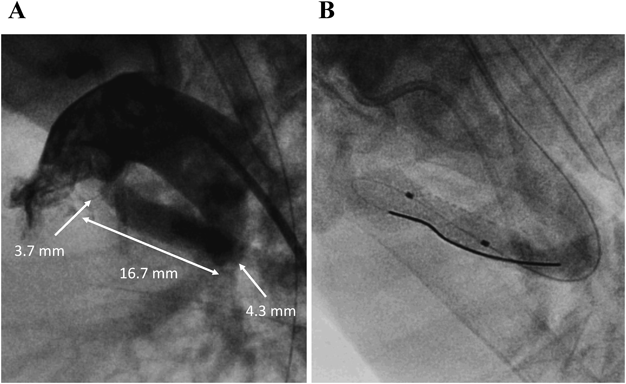

症例2は,DORV/PA, 18トリソミーで,開心術のリスクが高く生後11か月までプロスタグランジン製剤の持続投与を継続されていた.当初は積極的治療を行わない方針だったが,両親より在宅移行の希望を認め,DSを目的に他院から紹介された.生後11か月,体重4.8 kgで左総頸動脈穿刺によるDSを行った.動脈管は屈曲しており,MULTI-LINK 8® 4.0×12.0 mm(Abbott; Chicago, IL)を留置した(Fig. 3).その後の経過は良好で,速やかに在宅移行が可能だった.

Pediatric Cardiology and Cardiac Surgery 36(4): 294-305 (2020)

Fig. 3 Case 2: DS for DORV/PA, 18 trisomy

A) Lateral view of “straight” ductus arteriosus angiography revealed originating from thoracic aorta. B) Angiography after DS. DORV/PA: Double-outlet right ventricle/pulmonary atresia